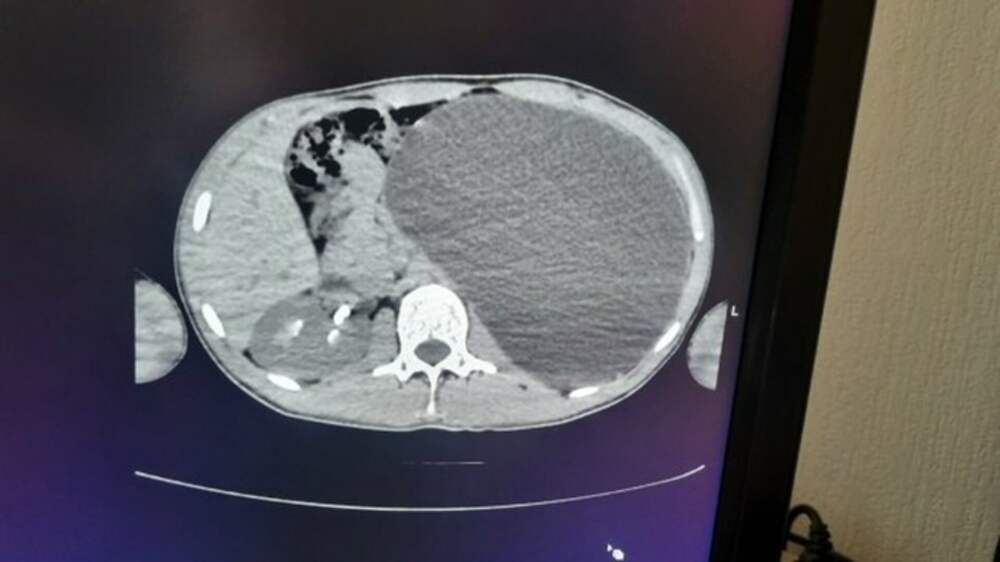

Размером с пятилитровую бутылку. Под Новосибирском подростку удалили гигантскую почку

Каких-либо жалоб на самочувствие у парня не было В Новосибирской области врачи провели сложную операцию 17-летнему подростку, у которого была обнаружена тяжелая патология почки. Об этом сообщили в пресс-службе регионального Министерства здравоохранения. Заболевание выявили во время... Далее